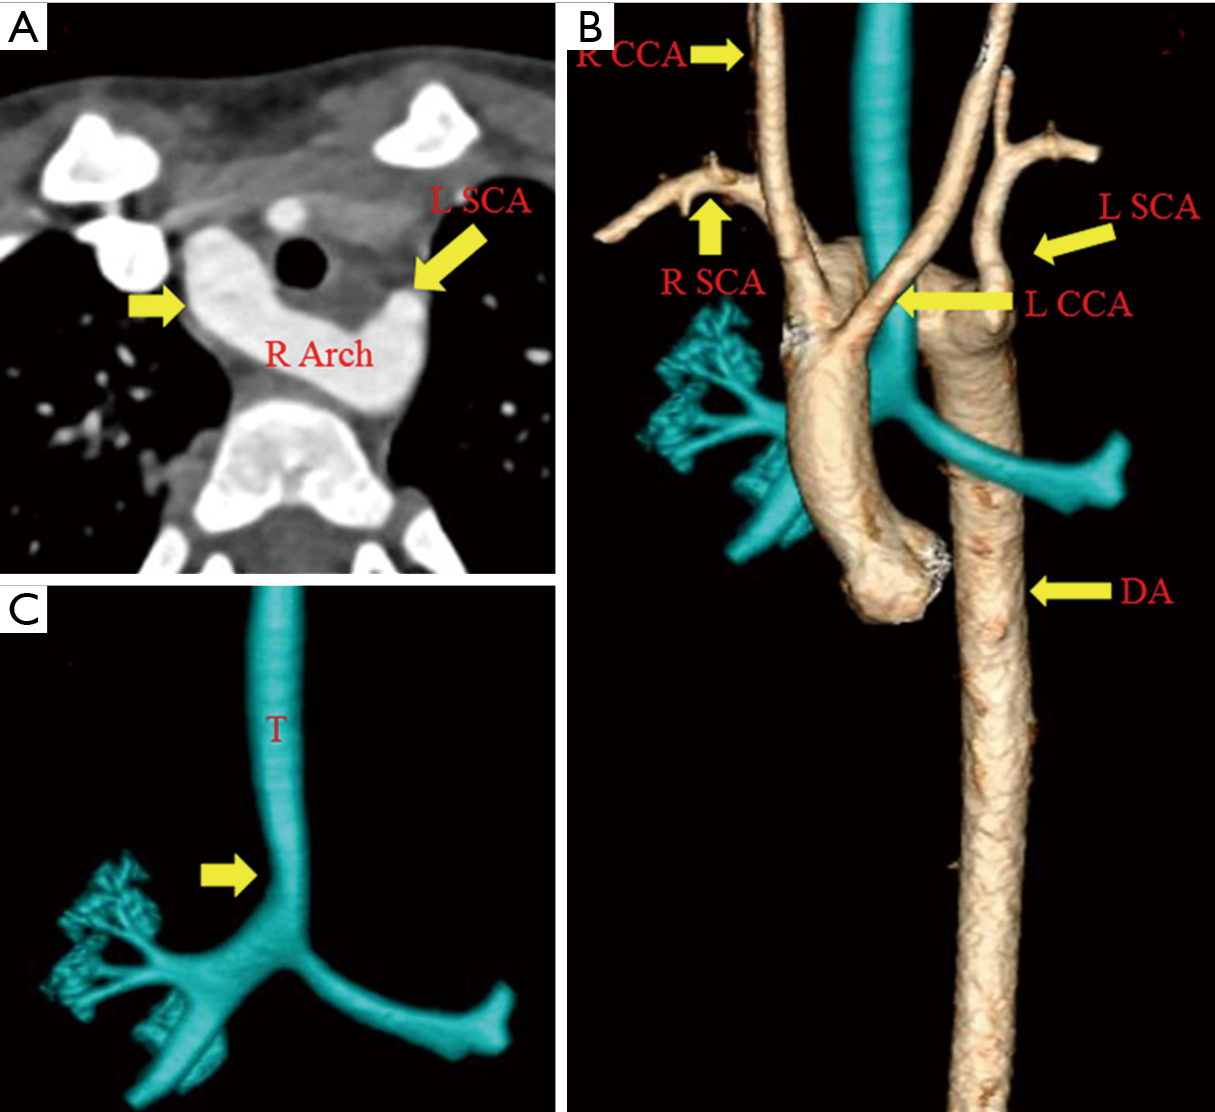

Clinical Value Of Multi Slice Spiral Computed Tomography Angiography And Three Dimensional Reconstruction In The Diagnosis Of Double Aortic Arch from www.spandidos-publications.com Atlas of the anatomy of the head and neck on a ct in axial, coronal, and sagittal sections, and 3d images. This video deals with the anatomy of the thorax in transverse anatomical and axial ct sections. Aortic arches are the arteries of pharyngeal arches that arise from aortic sac and terminate into dorsal aorta on each side.

Anatomic variations of the aortic arch depicted on 444 ct angiographies.